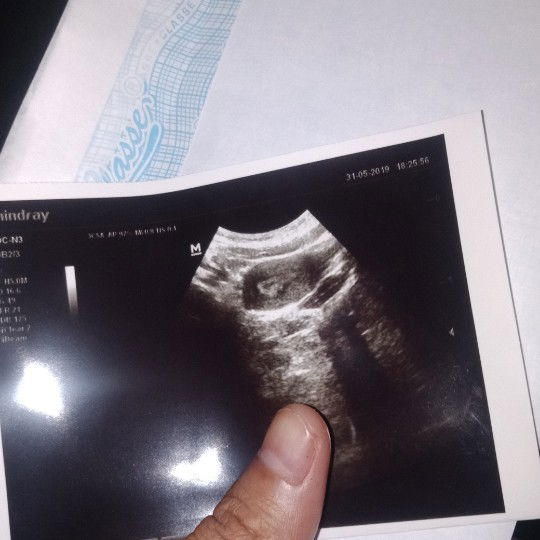

Hallo bunda usia saya jalan 22thn bulan januari 2019 sy baru saja keguguran pd usia kehamilan 5bln tapi tanpa kuret (karna aku takut hehe) Oiya aku kemarin usg ke dokter niat hanya hanya ingin mengecek udah bersih atau msh ada darah2 yg tertinggal pasca keguguran tanpa kuret kemarin.dokter bilang semua sdh bersih dan dinyatakan ada kantung kehamilan lagi(alhamdulillah dalam hati senang bgt pas dokter bilang gitu?) tapi aku tespack negatif begitu di usg lgsg ada kantung kehamilan lagi.pdhl sy tgl 9mei kemarin baru halangan selama 5hari pdhl sblmnya sy gak pernah halangan dgn waktu smpai 5hari biasanya 3 /4hari ajasi . kebetulan aku bulan april nya gak halangan bun sekalinya halangan lgsg ke bln mei. Dan skrg yg aku alamin perut terasa kembung,payudara nyeri,pipis terus,pinggang sakit . Apa bunda bunda dsni ada yg ngalamin seperti aku? Dan ini memang bnr hamil atau gmna ya? Terima kasih